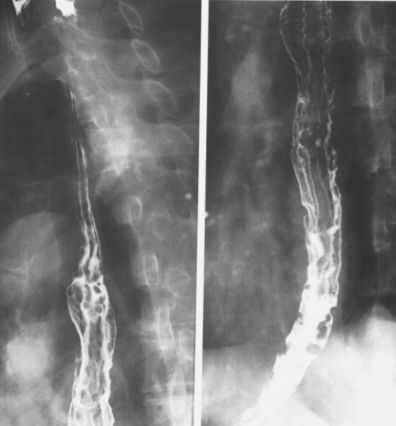

反流性食管炎:针尖样钡点、颗粒状改变。

反流性食管炎,食管下端呈现颗粒状